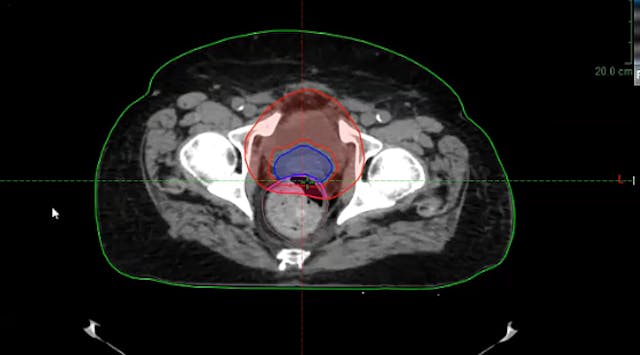

05/26/2022 - Dr. Ronald Chen - Radiation Oncology - GU

prostate cancer, local recurrence, PSA, ADT, fistula, cardiac comorbidity, brachytherapy, external beam radiation, high risk